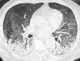

Acute respiratory distress syndrome (ARDS) is a type of respiratory failure characterized by rapid onset of widespread inflammation in the lungs. Symptoms include shortness of breath (dyspnea), rapid breathing (tachypnea), and bluish skin coloration (cyanosis). [Source: Wikipedia ]